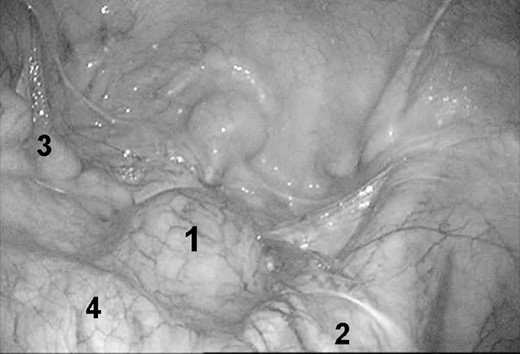

Under general anesthesia, the patient was placed in the supine position, and a 4-port technique was used. A 12-mm port was inserted through an umbilical incision for the placement of a flexible laparoscope. Three other ports (one 12-mm and two 5-mm ports for retraction or the working port) were placed. The left-sided port was mainly used for retraction. An initial incision was made in the retroperitoneum, and mainly sharp dissection by Liga-Sure was used to isolate the mass from the surrounding tissues. With careful dissection using sharp and blunt maneuvers, the mass was dissected from the neighboring vessels, such as the right internal iliac vessels and ureter (Fig. 5). Although the ureter was easily identified and dissected free, the mass strongly adhered to the right internal iliac vessels, making its dissection difficult. Sponge dissection was very useful in that situation. Once free from the surrounding tissues, the mass was placed into a plastic bag to avoid spillage into the abdomen. It was then received through the enlarged incision of the umbilicus. A suction drainage tube was placed into the pouch of Douglas through a 12-mm port in the right side of the abdomen.

Laparoscopic findings of schwannoma in the pelvis. 1, schwannoma 2, right ureter 3, rectum 4, right iliac vessel.